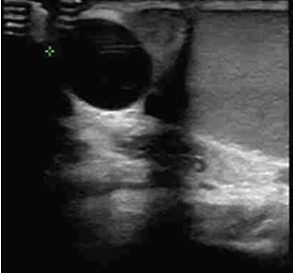

患者,男,27岁。 主诉:婚后9个月未育。 现病史:患者结婚9个月,正常房事,未曾行避孕措施,一直未育。2015-8-10于我院行精液常规未见精子。2015-8-11我院阴囊彩超示双侧附睾头囊肿,左右大小分别约为1.4*1.1cm,1.4*1.2cm。经直肠前列腺彩超示:前列腺呈炎性改变,右侧精囊正常,左侧精囊囊肿,大小约为3.2*2.2cm。性激素全套未见异常。2015-8-14复查精液常规仍未见精子,抑制素B定量为207.33pg/ml。2015-9-24精浆生化示:前列腺存在疾患,该病人属于梗阻性无精症,精囊缺如。门诊以射精管梗阻收入我科。 既往史:幼时曾有腮腺炎。